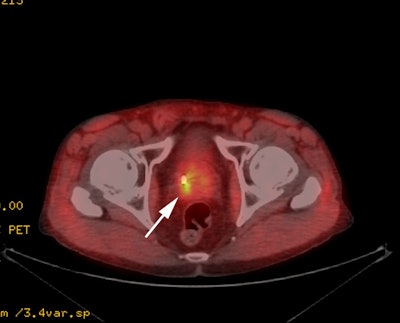

Biochemical recurrence:

The agent can also be used for the evaluation of patients with

suspected biochemical recurrent prostate cancer [46]. Conventional imaging

underestimates lymph node disease in patients with biochemical

recurrence [80]. Only 11-14% of patients with biochemical

failure after radical prostatectomy have positive CT findings

[80]. 68Ga-PSMA PET CT can identify disease

outside of the prostate bed in 28-43% of men with rising PSA

following radical prostatectomy [82]. In one study, only 48% of

all 68Ga-PSMA PET positive nodes were pathologic by

size criteria on CT [80].